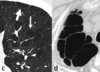

80

Patrón en panal

Patrón intersticial bibasal

82